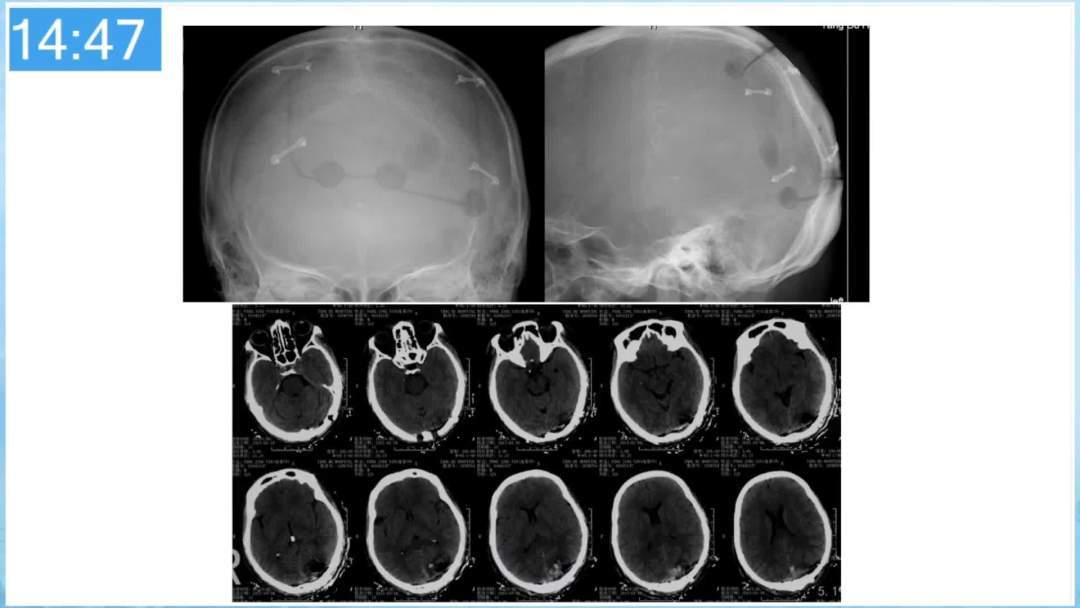

本期为大家特别分享:空军军医大学唐都医院邓剑平教授的精彩会议内容《颅内动静脉畸形的复合手术治疗》,欢迎大家阅读和分享!